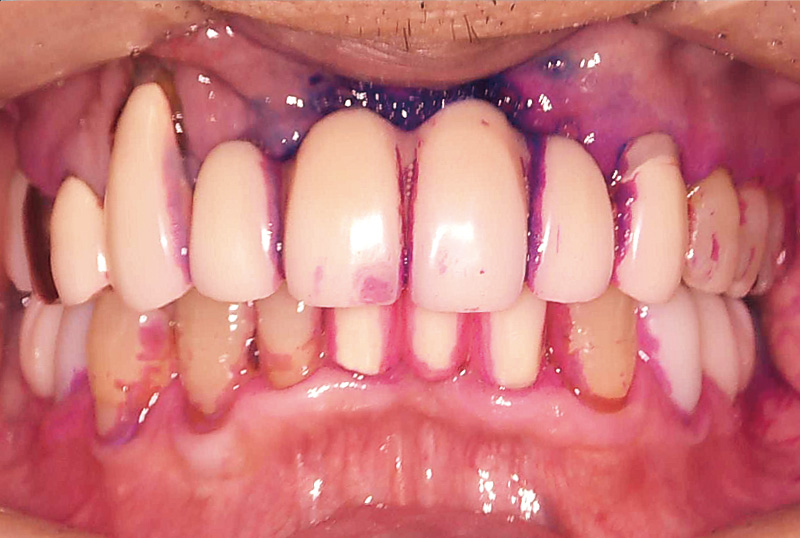

症例の患者さんは、奥様の介護があり毎日忙しくされていることもあってか、とにかくプラークコントロールが不良で、改善の兆しが見えませんでした。初診から6年が経過し、その間補綴治療を行ってきましたが、相変わらず磨き残しは目立っていました(図3)。そのため、染め出し後に「PrimescanConnect」でスキャンしたデータをお見せしたところ、「こんなにも磨き残しがあるとは思ってなかった」と、とても驚かれ、それ以降セルフケアの意識が向上し、磨き残しは大幅に減少しました(図4~6)。

図4 初診から6年後。染め出し後に「PrimescanConnect」によるデジタルスキャンデータをお見せすると、残存プラークの多さに大変驚かれた。 -